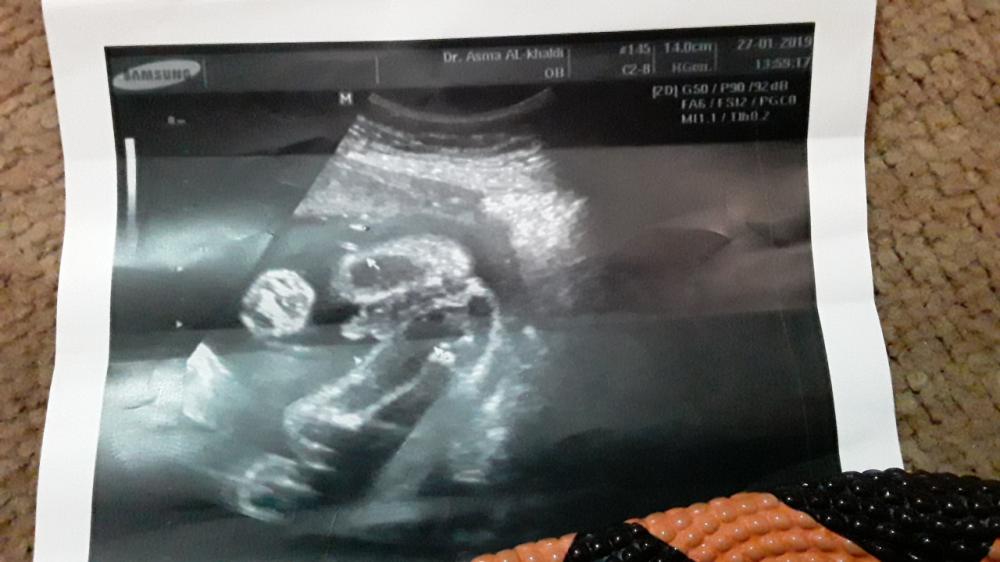

هاي صورة سونار محمد

هاي صورة سونار محمد ان شاء لله الله يجبر خاطري يجبر خواطركم والي فرحني يفرحكم جميعا عاجل غير اجل